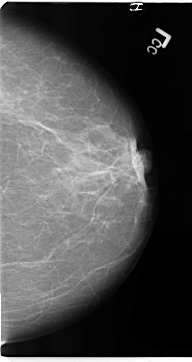

B_3137_1.RIGHT_MLO

RIGHT_MLO LINES 4648 PIXELS_PER_LINE 2712 BITS_PER_PIXEL 12 RESOLUTION 50 NON_OVERLAY